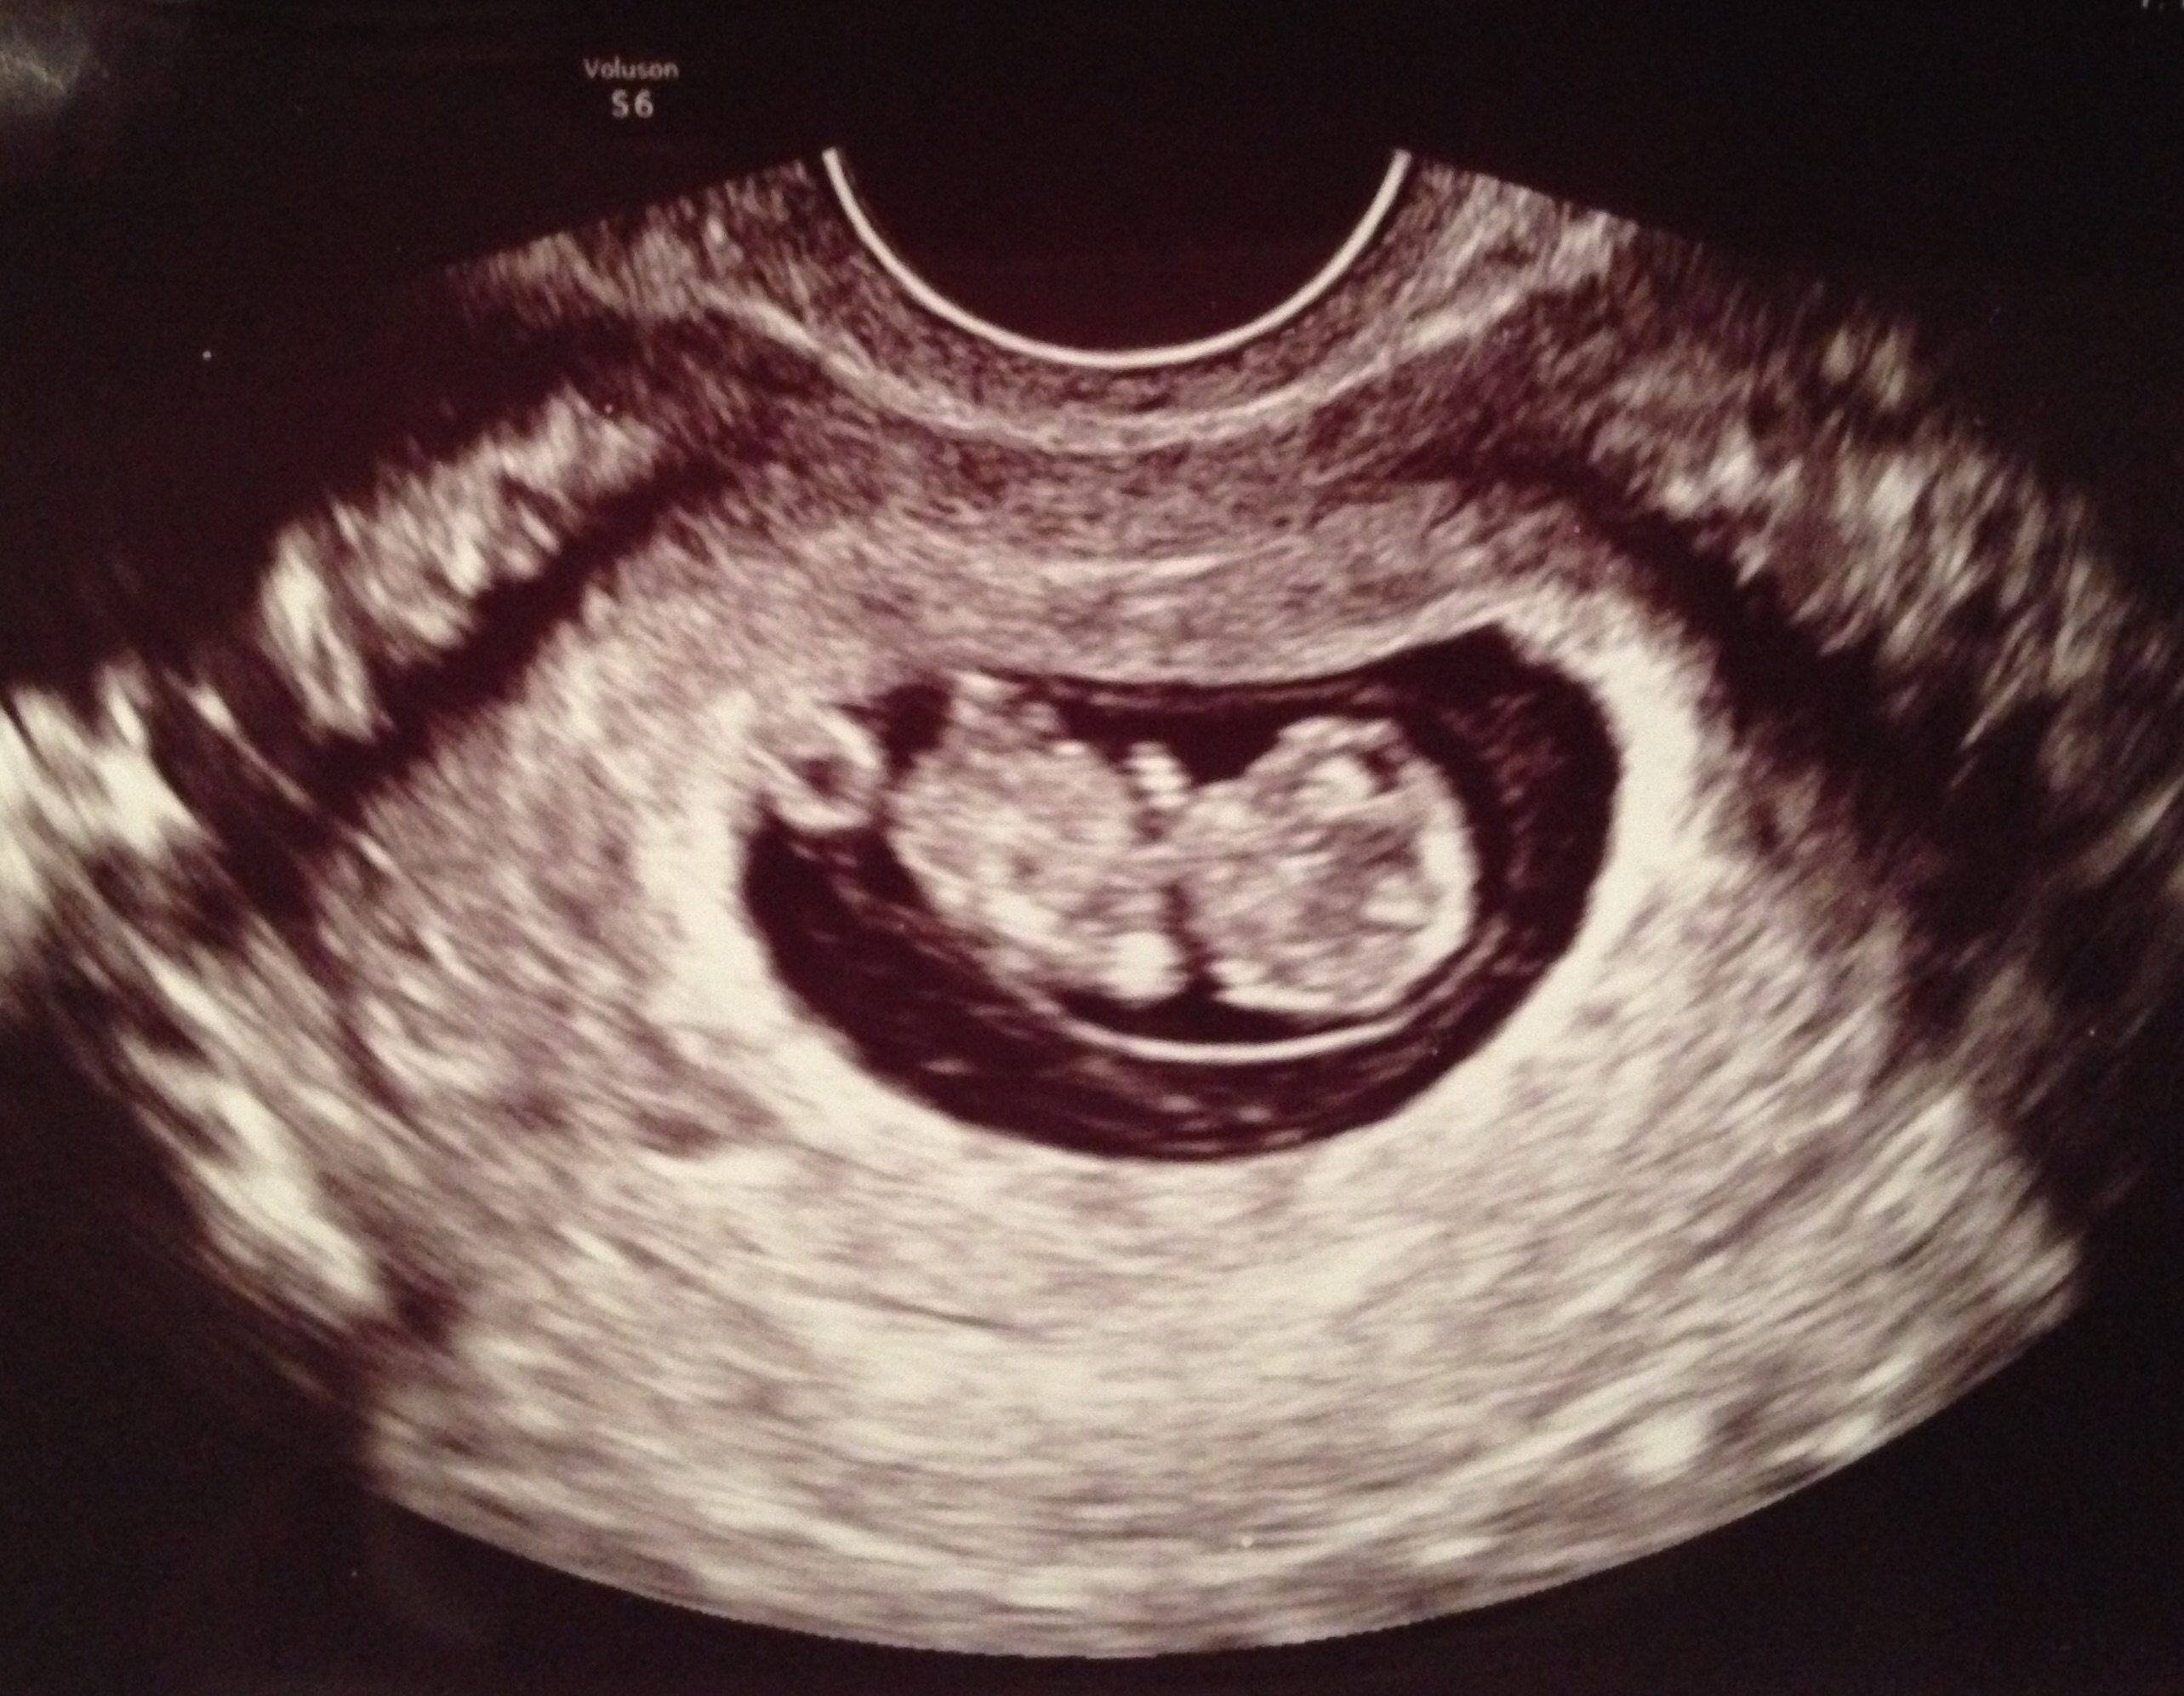

FTM! So excited to see how much my little gummy bear has grown in two weeks! 1st pic is at 6w5d, HR 147, and just a little blob with a flickering heart. 2nd & 3rd pics are at 8w5d, HR 176, and looked so much like a tiny baby with bitty arms and legs. Doc says baby is healthy and quite a dancer, it was moving and waiving all over the place. What a blessed moment to see!